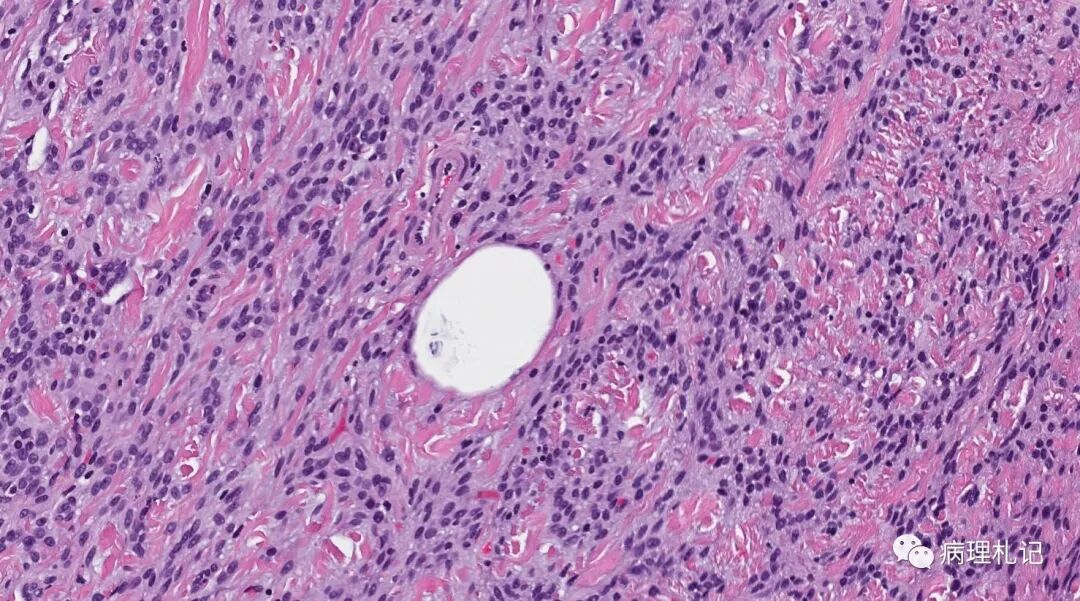

乳腺癌病理he切片

常见浸润性乳腺癌